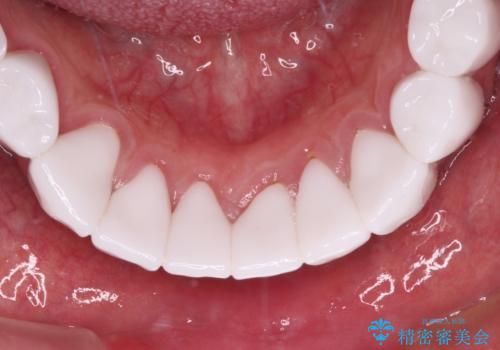

とにかく作り物のような真っ白な歯にしたい フルジルコニアクラウンによる補綴治療

不自然なくらい真っ白にしたいとのことでしたので、透明感のないフルジルコニアクラウンを用いて補綴することとしました。

本来、あまりにも不自然な歯となるため、フルジルコニアクラウンを前歯に使用することは、咬合力が強すぎる場合を除き、ほとんどありません。

それでも、色調、形態ともに不自然なくらい真っ白な歯をご希望でしたので、患者様には大変満足していただきました。